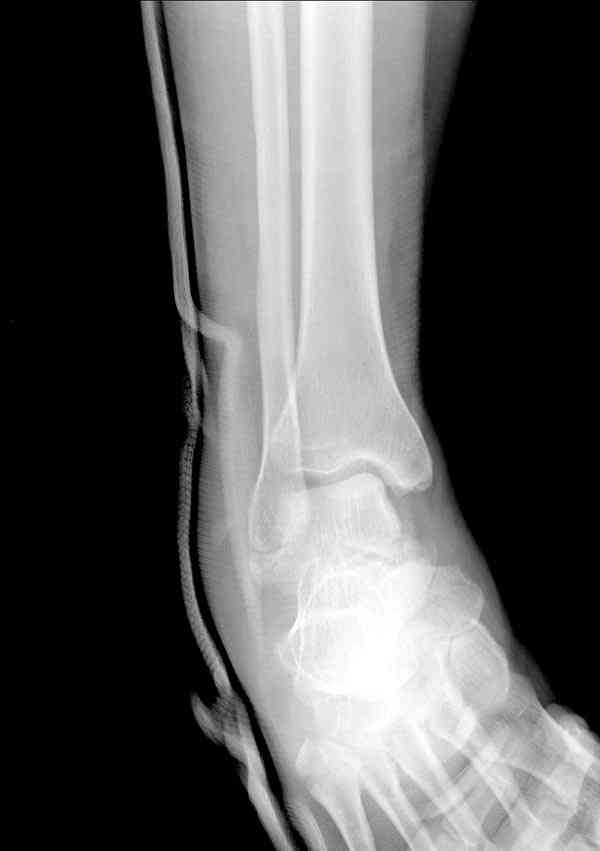

Interesting case

The ankle joint looks ruined. I wonder howcome is it as ruined after 2 days. I would open the joint( Some people would artroscope it) and judge the osteosynthes vs ankle fusion according to the ankle joint condition. The subtalar does not look injured, but if you feel there is a clinical

problem- CT it. Above all- when I see such an X-Ray I call the resident who ordered it and tell him that I would expect him first thing to reduce it on arrival since the soft tissue suffer and I hope that currently the p-nt is reduced to some extent at least.

Sorry- I revised it and the talus is fractured- take him to the theater at once and reduse it with Int Fix

The soft tissue will be a problem- Ex Fix will be better thn plaster

а основании двух видов ренгенограмм невозможно радикально решить о необходимости открытой репозиции или первичного артродеза.

Для оценки состояния нужны дополнительные исследования, например Canale или Broden ренгенограммы и Компьютерная томография.

В вашем случае доступ через перелом медиальной лодыжки, обычный доступ через остеотомии лодыжки, где имеется возможность прямой репозиции тарана, после фиксации шурупами, лодыжки фиксируются обычным 2х лодыжечным методом.